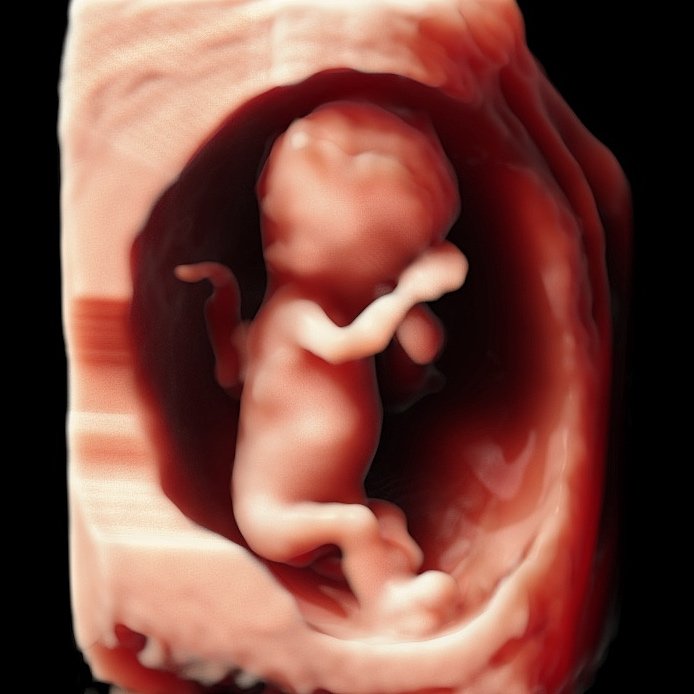

In 3&4D de baby zien blijft natuurlijk heel erg bijzonder. Samen met de familie kijken op wie de kleine lijkt en wat er allemaal in je buik gebeurd is zo speciaal. Het maakt het allemaal nog echter, omdat het soms zo moeilijk te bevatten is dat er zo’n klein wonder in je groeit. De mooiste periode om de baby in 3&4D te bekijken is tussen de 27 en 30 weken zwangerschap.

Ook na de 30 weken maken we vaak nog hele mooie beelden, het is natuurlijk ook gewoon een beetje geluk hebben. Dus mocht je twijfelen kom dan altijd gewoon proberen, mocht het niet lukken en denken we dat het ook niet meer gaat lukken, dan betaal je alleen de even spieken echo!